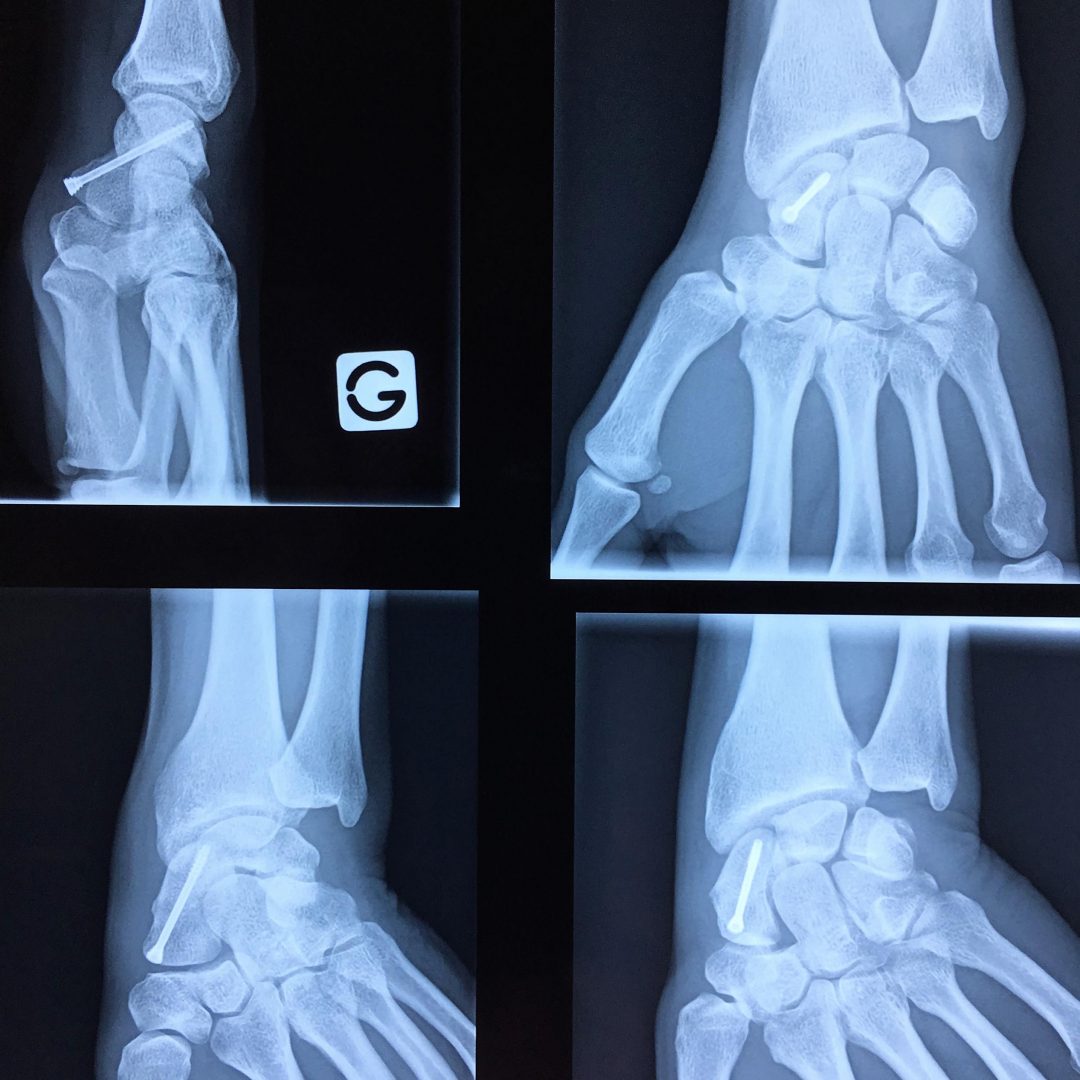

Fracture du scaphoïde Fiche santé HCL Le temps de reconsolidation de cet os assez mal vascularisé est long et varie en fonction des différents types de fractures et du traitement mis en place Une étude a constaté que les plâtres en cas de fracture du scaphoïde génaient la conduite automobile Le temps de reconsolidation de cet os assez mal vascularisé est long et varie en fonction des différents types de fractures et du traitement mis en place

Source: mannlichmls.pages.dev Fracture du scaphoïde Urgences de la main à Paris , Le temps de guérison va dépendre du type de fracture et du fait qu'elle soit déplacée Une fracture scaphoïde non déplacée, c'est-à-dire sans diastasis interfragmentaire, nécessite un temps de guérison moindre que dans le cas d'un déplacement ou d'une fracture du pôle proximal impliquant une chirurgie

Source: sfracksozw.pages.dev Fracture du scaphoïde et ses complications L'institut de chirurgie de la main de l'ouest parisien , Le délai de consolidation varie en fonction de la localisation de la fracture Temps de guérison d'une fracture du scaphoïde non déplacée

Source: codylanehxc.pages.dev Fracture du scaphoïde Bordeaux Institut Aquitain De La Main , La durée de consolidation est assez classique : il faut entre 6 et 8 semaines à l'os pour commencer à être bien consolidé. Le délai de consolidation varie en fonction de la localisation de la fracture

Source: ckirschzbw.pages.dev Fracture du cassé) temps de guérison & avis kiné , En général, on estime que l'os prendra entre 8 à 12 semaines avant de guérir. Le tiers distal devrait guérir en 6-8 semaines, le tiers moyen en 8-12 semaines et le tiers proximal en 12-24 semaines

Source: variletsstu.pages.dev Fracture du scaphoïde et ses complications L'institut de chirurgie de la main de l'ouest parisien , Le tiers distal devrait guérir en 6-8 semaines, le tiers moyen en 8-12 semaines et le tiers proximal en 12-24 semaines Une étude a constaté que les plâtres en cas de fracture du scaphoïde génaient la conduite automobile